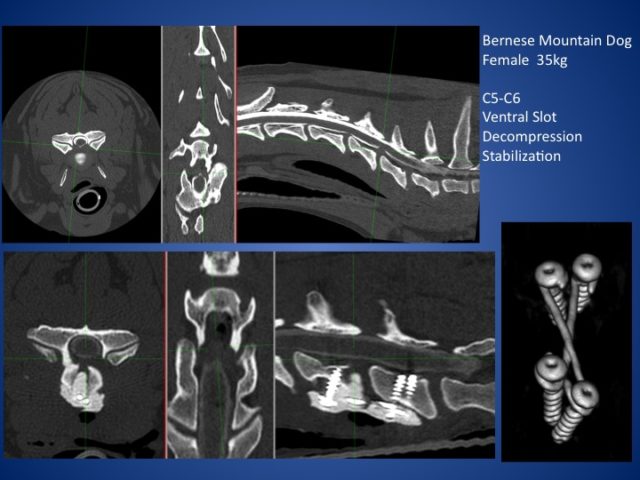

ウォブラー症候群

大型犬の尾側頚椎が不安定になる病気です。

ワイマラナー、ラブラドール、ドーベルマンなどに多く認められます。

椎体の奇形、椎間板ヘルニアが併発している事があります。

症例はベントラルスロットと腹側固定術と背側椎弓切除により減圧術を行っています。